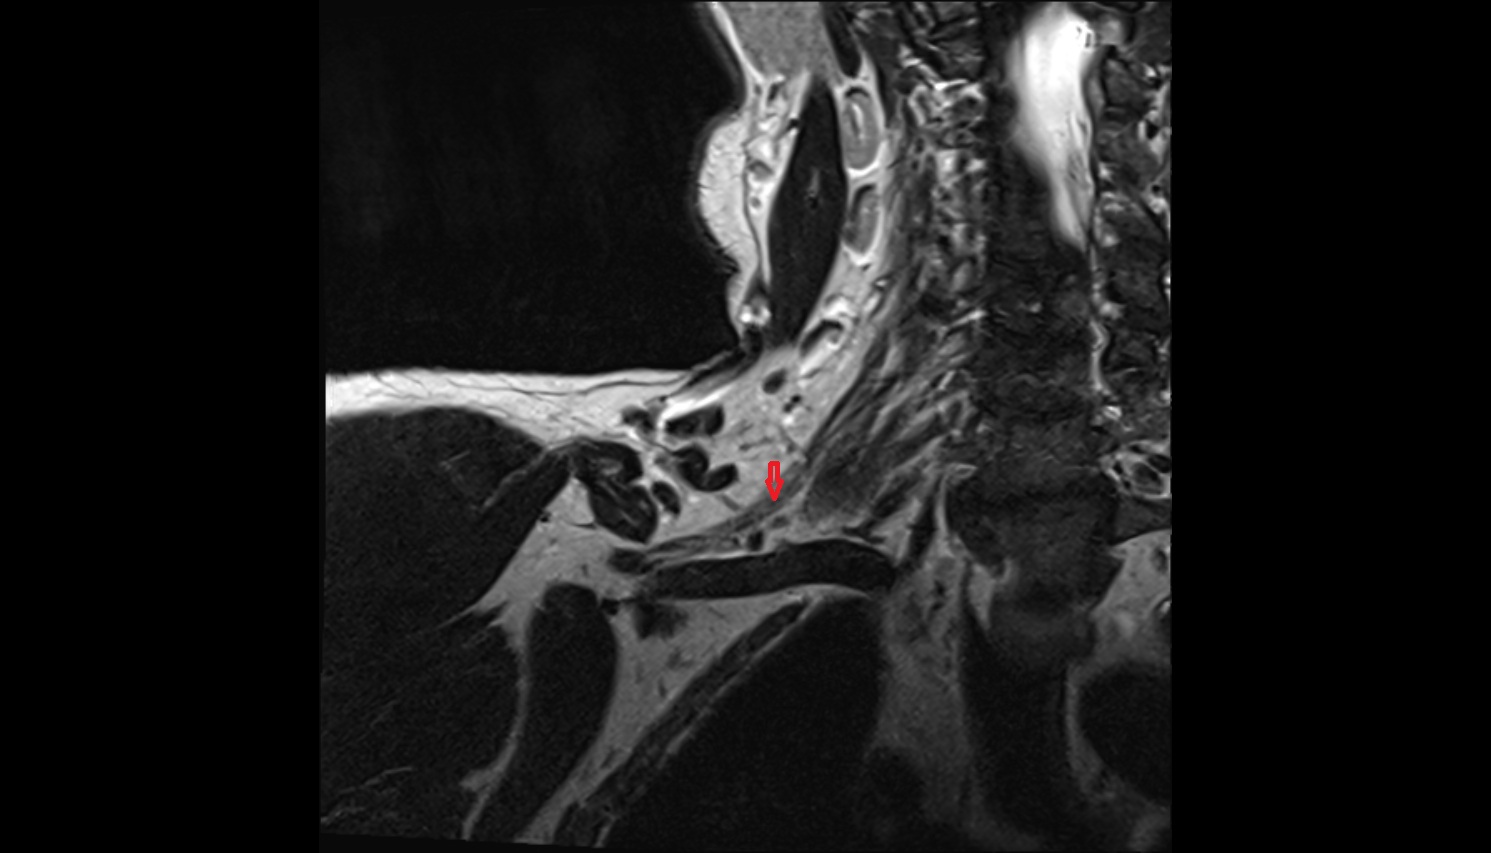

- Hip joint